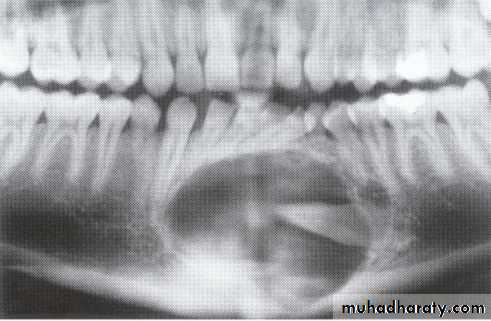

Ameloblasoma*Non-metastasizing tumor originating from remnants of the odontogenic epithelium of the enamel organ or dental lamina. *Associated with the crown of impacted teeth.

*80% located in the bicuspid & molar regions.

*Shape: is either unicystic or soap bubble-like lesion, Expansile, *Tooth migration is common,teeth in the area are vital.

*Adjacent teeth displaced, loosened , often resorbed

Extensive expansion in all dimensions

Maxillary lesions can extend into the paranasal sinuses, orbit or base of the skull.

Male > female.

Age; > 30 years

Dentigerous CystIt forms around the crown of an unerupted or supernumerary tooth at CEJ.

Some dentigerous cysts are eccentric, developing from the lateral aspect of the follicle so that they occupy an area beside the crown instead of above the crown.

It displace and resorb adjacent teeth.

It commonly displaces the associated tooth

in an apical direction.